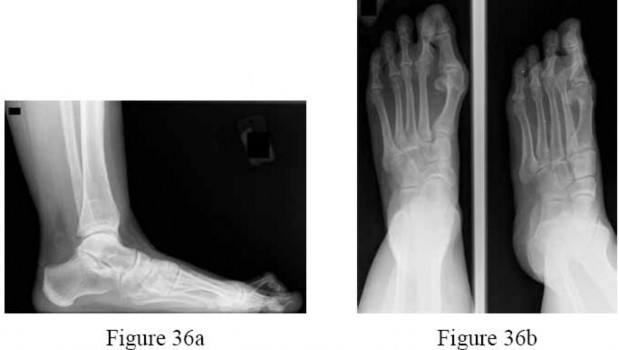

A 30-year-old female sustains a midfoot injury after falling from a horse. Radiographs demonstrate diastasis between the bases of the 1st and 2nd metatarsals. In a normal anatomic state, the native Lisfranc ligament originates and inserts on which two bony structures?

Explanation

The Lisfranc ligament is a stout, obliquely oriented intra-articular ligament that acts as the primary stabilizer of the second tarsometatarsal joint complex. It connects the lateral aspect of the medial cuneiform to the medial aspect of the base of the second metatarsal. Importantly, there is no direct ligamentous connection between the bases of the first and second metatarsals.